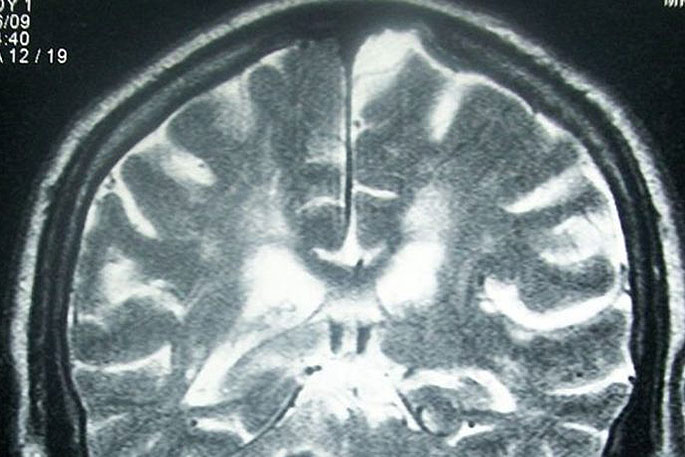

Girl's fatal tumour missed on scan

A district health board has been asked to review its radiology department, after a teenage brain cancer patient's MRI scan was misread and she later died. The teenager... Read More